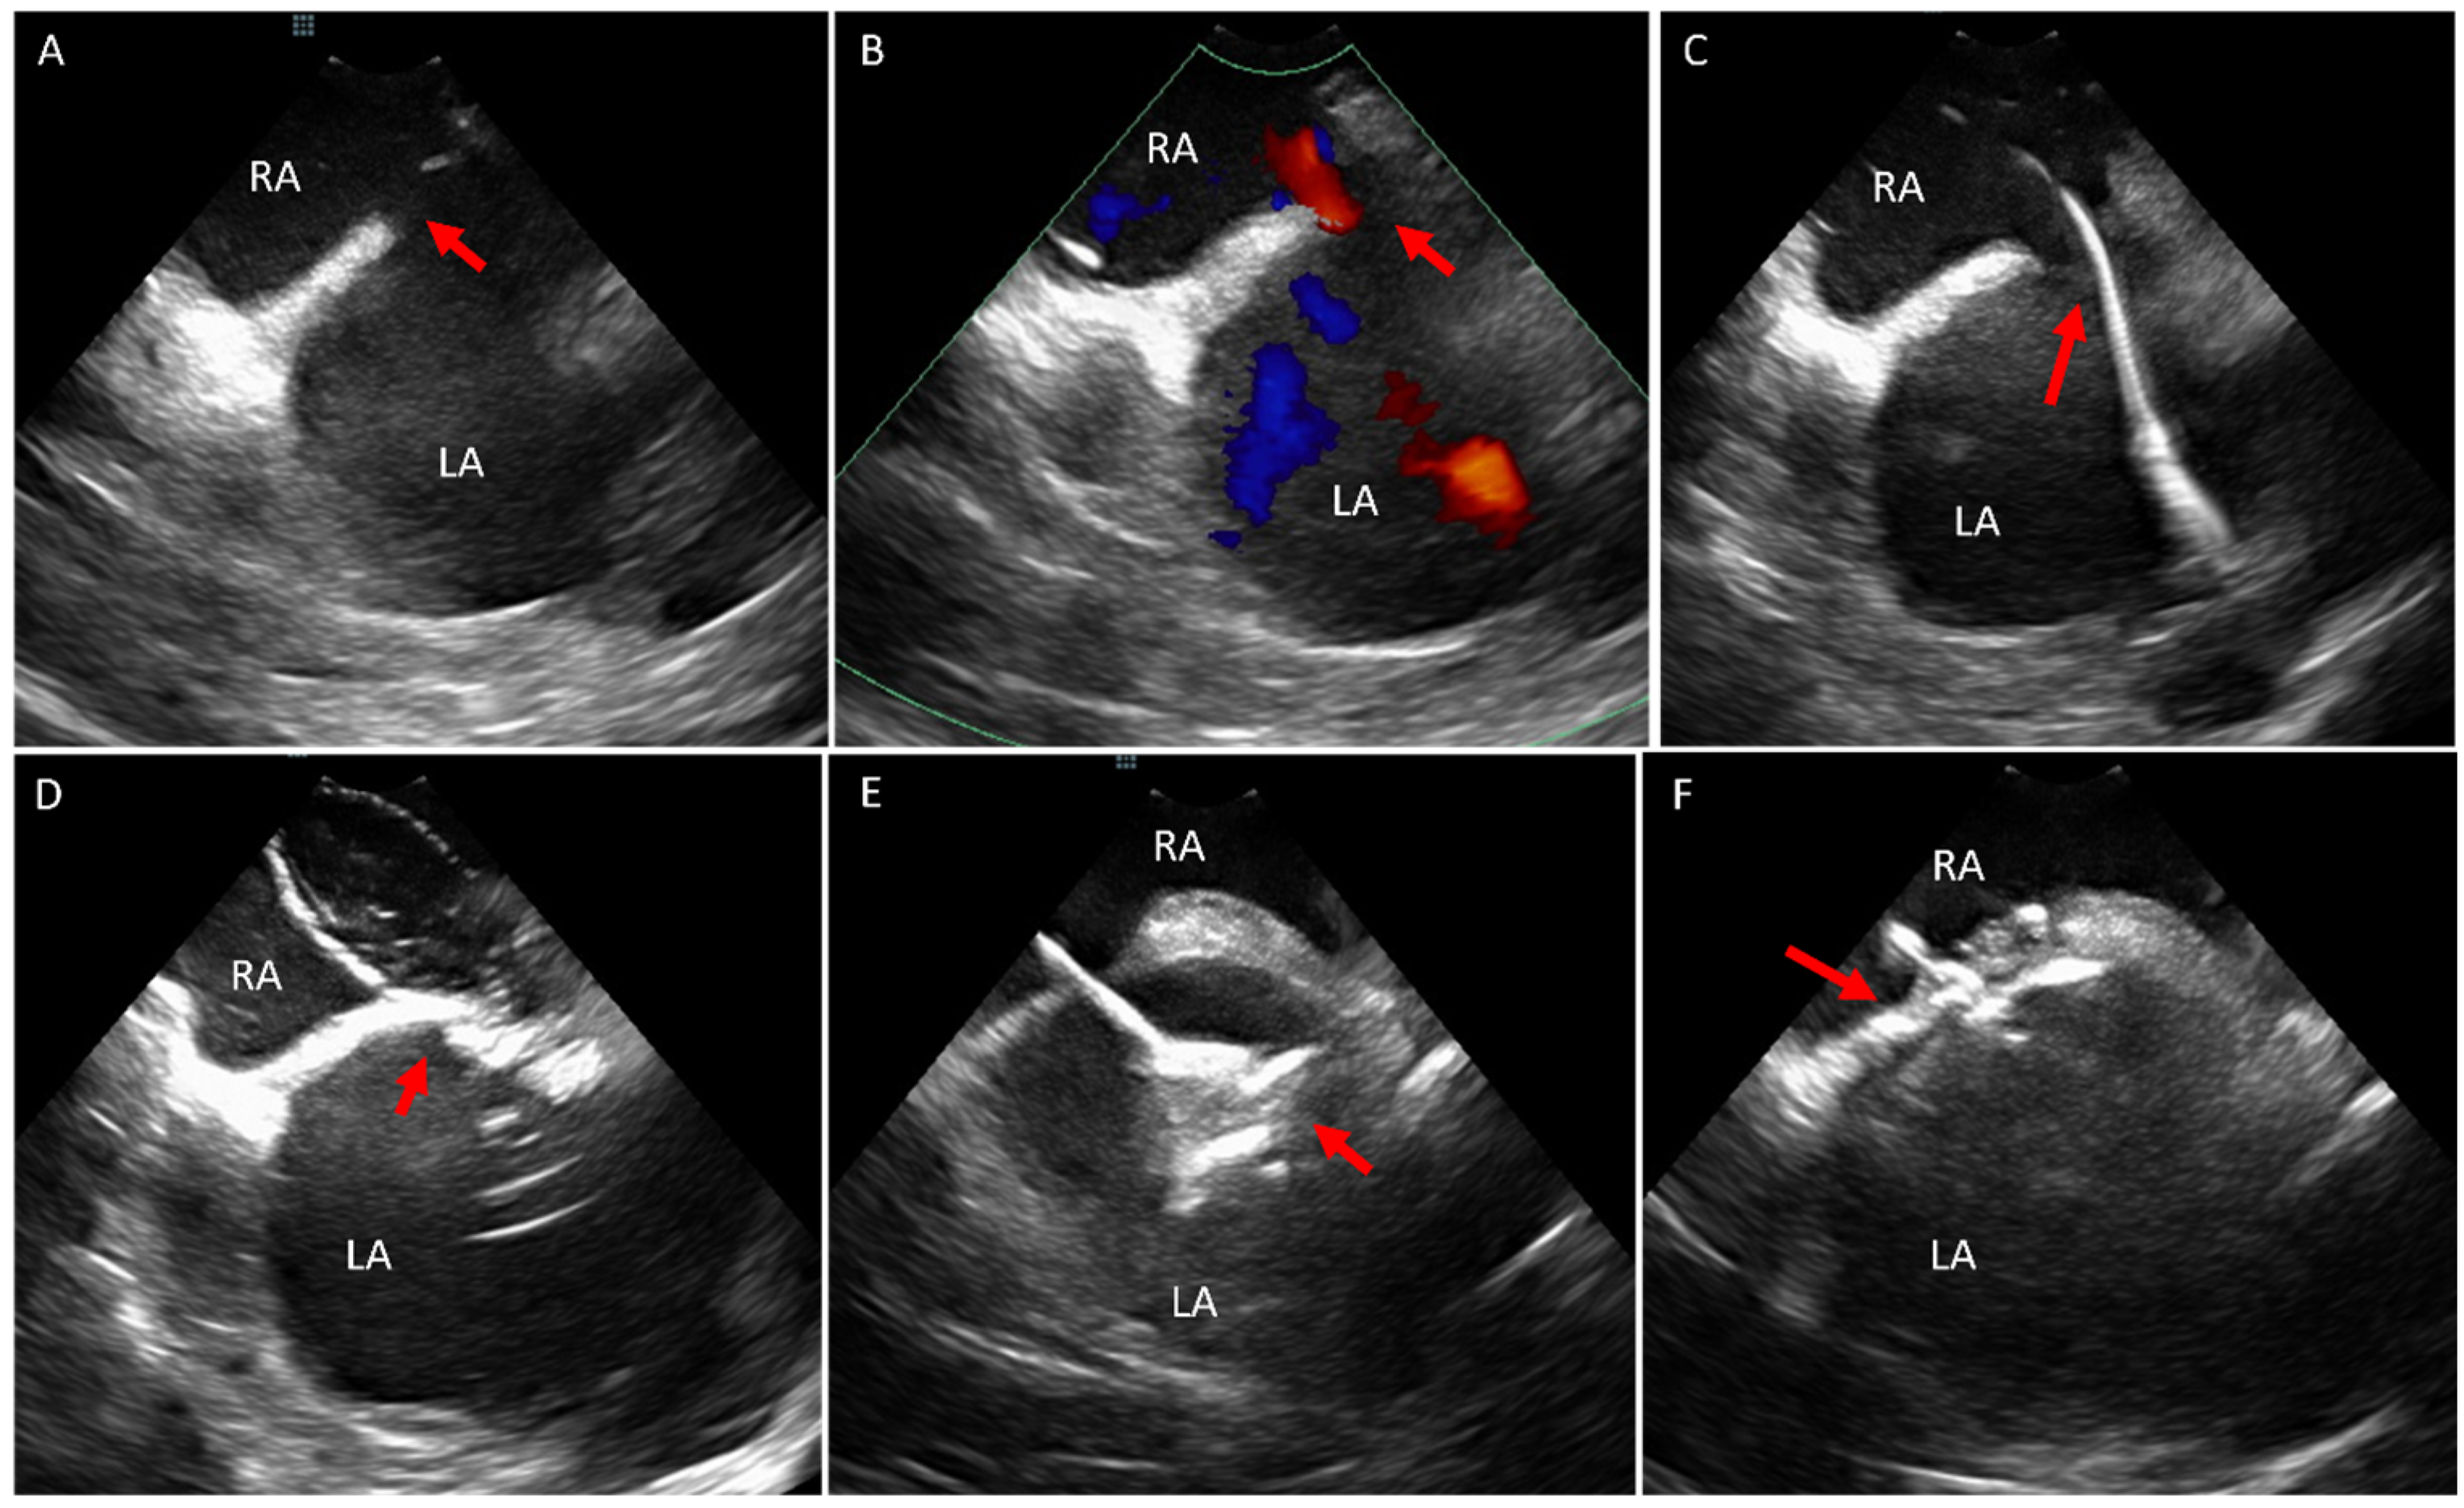

3. Ostium Secundum Atrial Septal Defect (ASD) and Patent Foramen Ovale (PFO) Closure